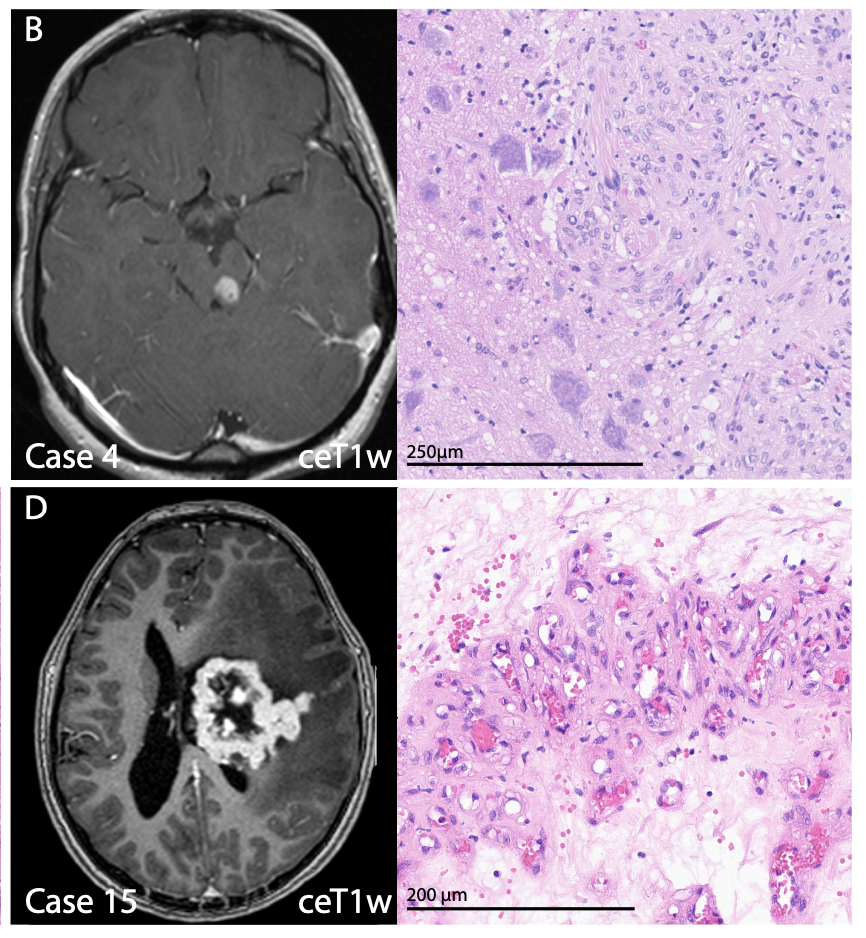

VGLL

VGLL fusions define a new class of intraparenchymal central nervous system schwannoma

Simone Schmid, Kanish Mirchia, Anna Tietze, Ilon Liu, Christin Siewert, Jakob Nückles, Jens Schittenhelm ... David TW Jones, David Capper

Neuro-Oncology · 2025 · doi:10.1093/neuonc/noae269